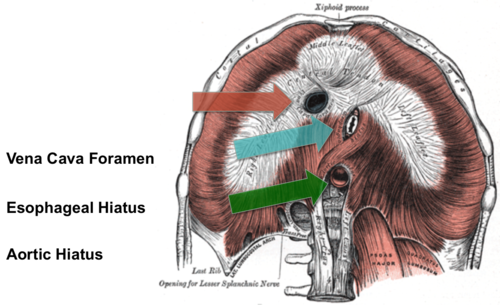

Diaphragma

Inandning

Foramen venae cava

röd pil

Hiatus aorticus

grön pil

Hiatus esophagus

blå pil